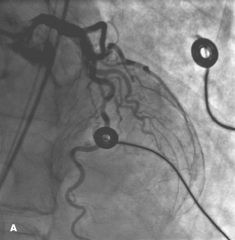

Ibrahim M. Elali, MD; Jose C. Missri

<p>The acute onset of substernal chest pain during vigorous exercise prompted a 70-year-old woman to seek emergency medical attention. She reported chest pressure, left arm numbness, shortness of...